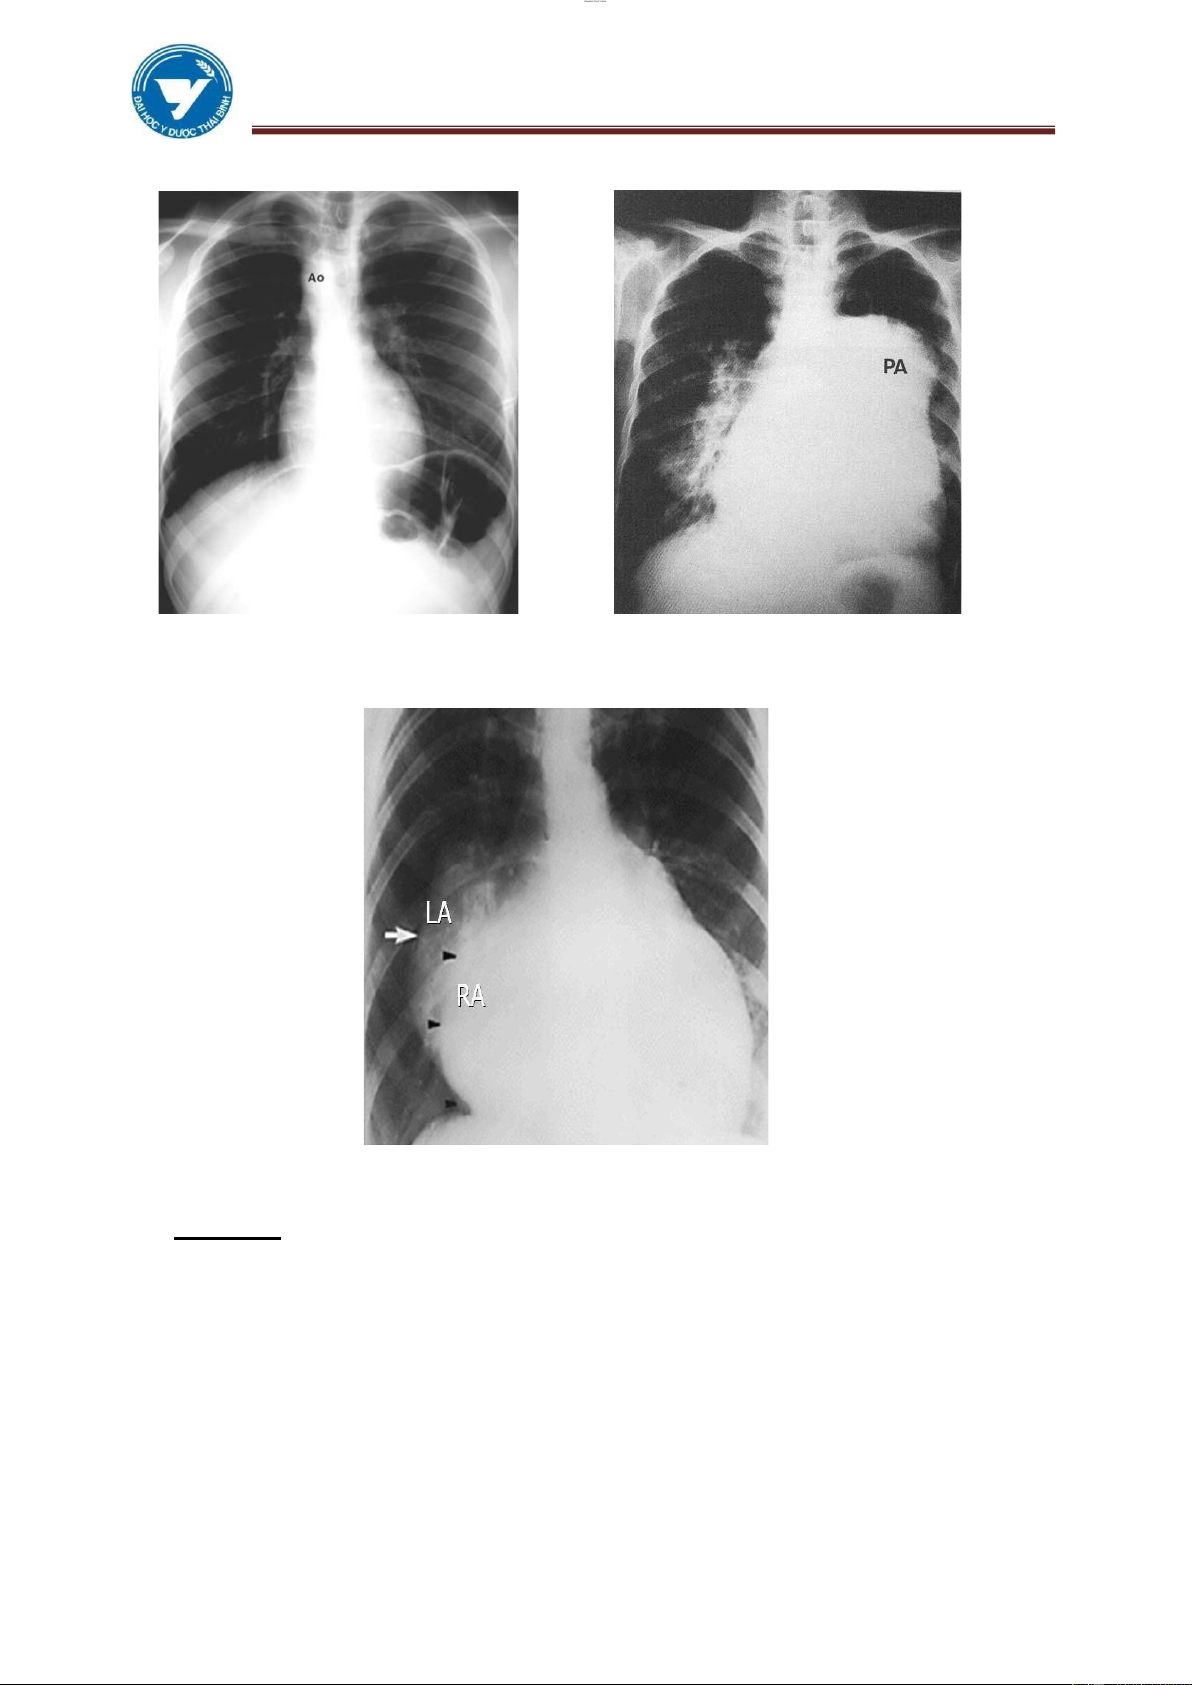

Hình 3.1: Các bờ và các cung tim tư thế

Hình 3.2: Các bờ và các cung tim tư thế thẳng nghiêng trái

Hình 3.3: Các bờ và các cung tim tư thế

Hình 3.4: Các bờ và các cung tim tư thế

chếch trước phải chếch trước trái

1.2.1. Tư thế thẳng: Các buồng tim chồng lên nhau tạo nên những bờ (phải, trái).

Trên mỗi bờ có các cung. Bờ phải:

Cung trên: Tĩnh mạch chủ trên, oạn lên quai ĐMC ở người già. Cung dưới: Tâm nhĩ phải. Bờ trái : Cung trên: Quai ĐMC.

Cung giữa: Động mạch phổi.

Cung dưới: Tâm thất trái.

1.2.2. Tư thế nghiêng: chủ yếu ể xem bờ trước, sau Bờ trước: Cung trên: Quai ĐMC.

Cung dưới: Tâm thất phải. Bờ sau: Tâm nhĩ trái 1/3 trên.

Tâm thất trái 2/3 dưới. Cửa sổ chủ phổi.

1.2.3. Tư thế chếch trước phải: xem 4 buồng tim.

1.2.4. Tư thế chếch trước trái: xem quai ộng mạch chủ, cửa sổ chủ phổi. lOMoAR cPSD| 22014077 lOMoAR cPSD| 45148588